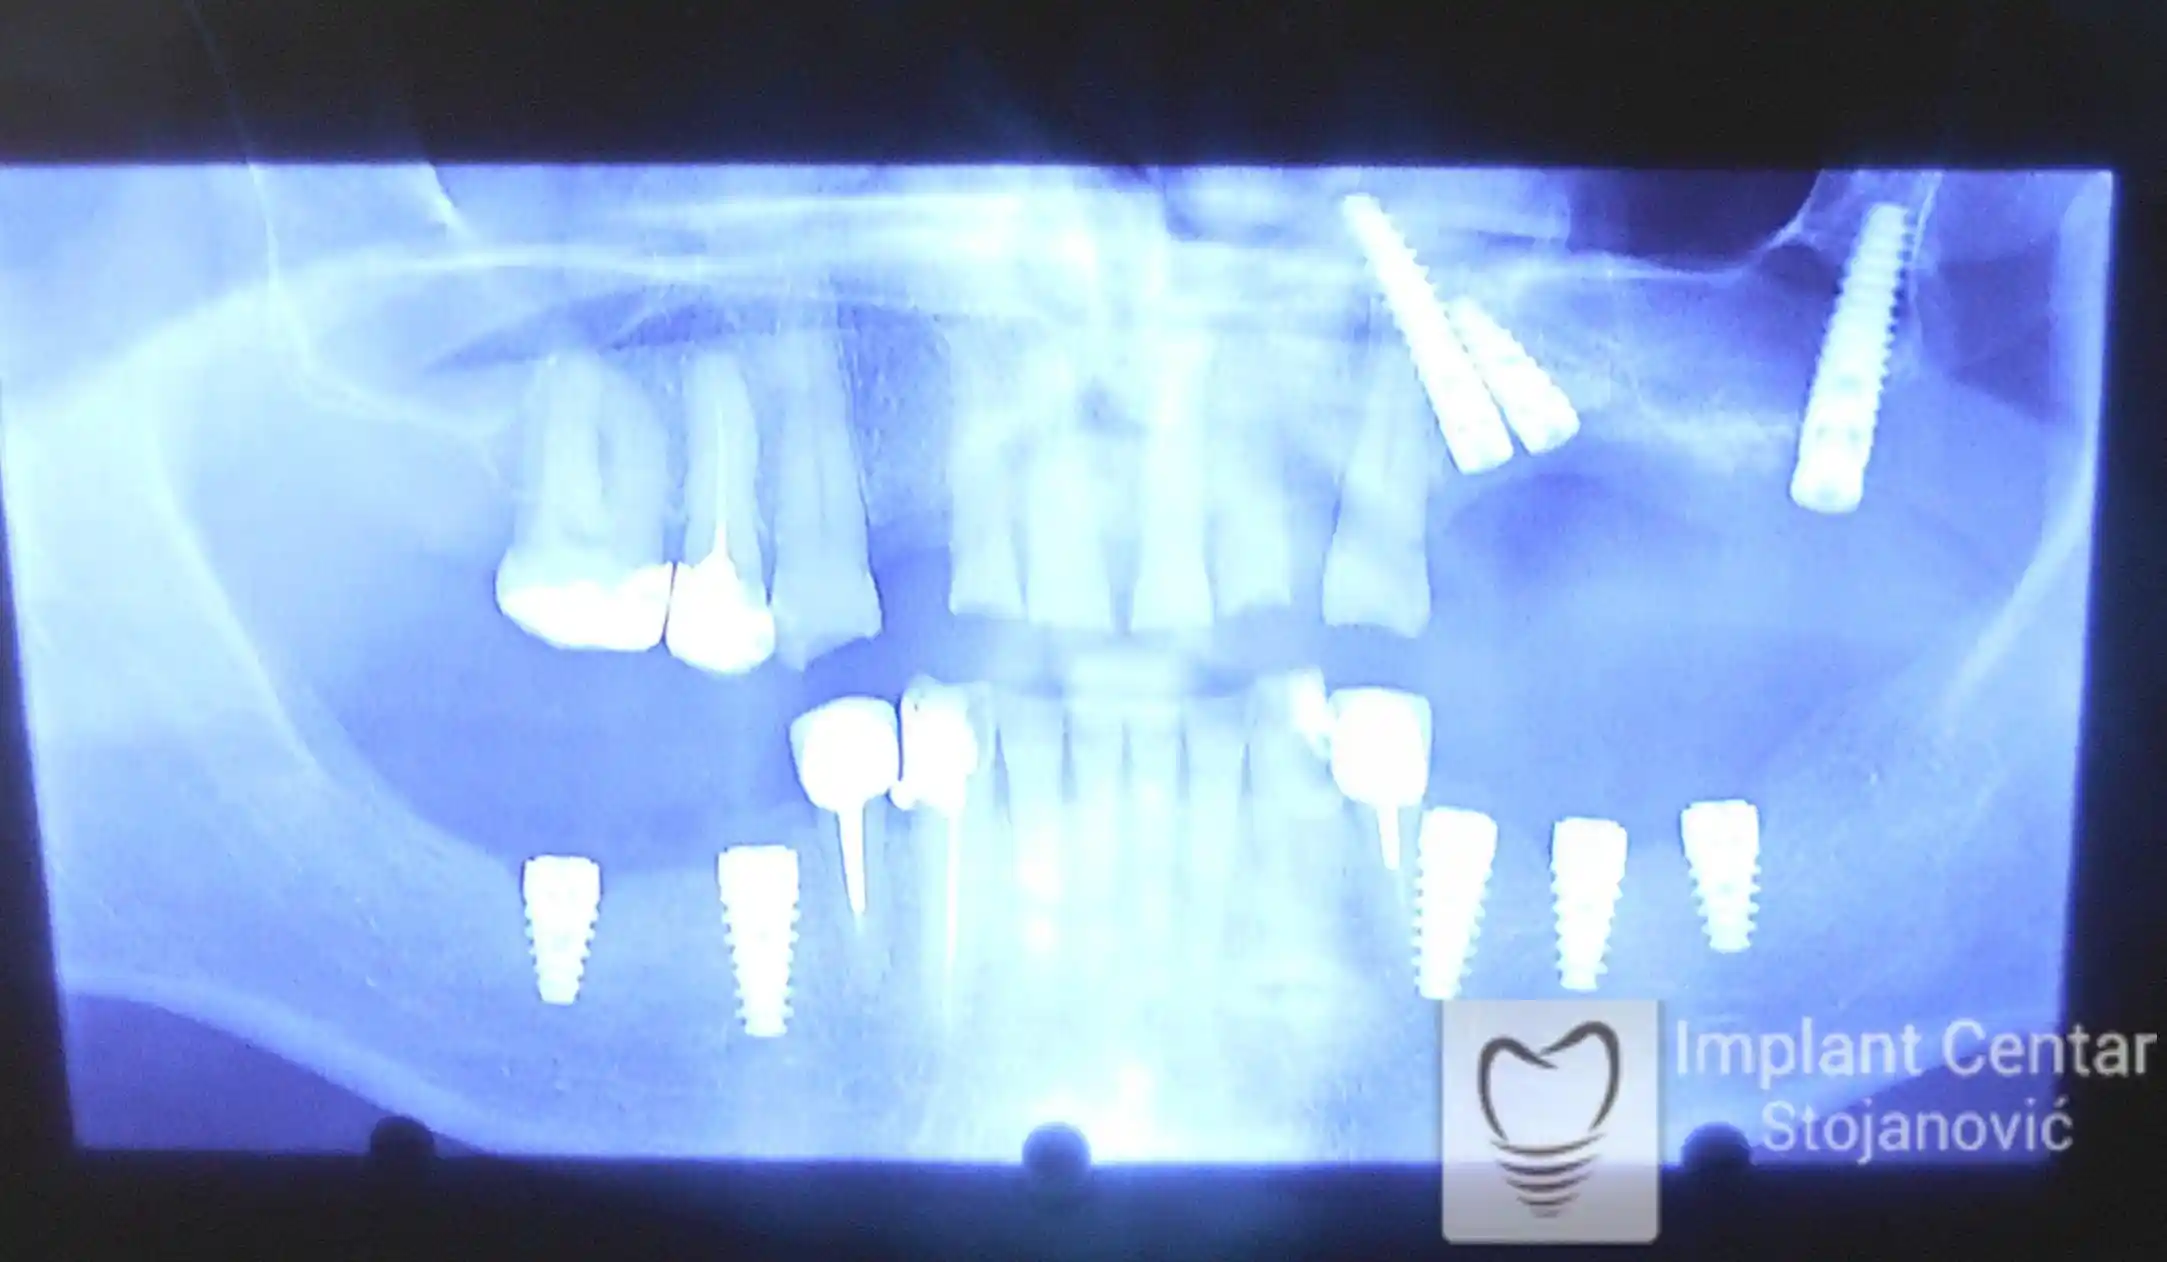

Na slici 1. slici 2. vidi se početno stanje — pacijent je imao prirodne zube, ali samo izradom novih mostova nije bilo moguće postići normalan odnos gornjih i donjih zuba (eugnatan zagrižaj).

Zbog toga je plan terapije uključivao vađenje svih preostalih zuba i ugradnju implantata u gornjoj i donjoj vilici. U gornjoj vilici postavljena su i dva tuberopterigoidna implantata, kao zamena za sinus lift proceduru, što se može videti na ortopan snimku nurađenom odmah nakon ugradnje (slika 3).

Već tri dana nakon operacije, pacijent je zbrinut fiksnim privremenim zubima na implantatima, čime je odmah povraćena funkcija i estetika osmeha.

Nakon završetka perioda integracije implantata, izrađeni su cirkonijum-keramički mostovi u gornjoj i donjoj vilici (slika 6.).